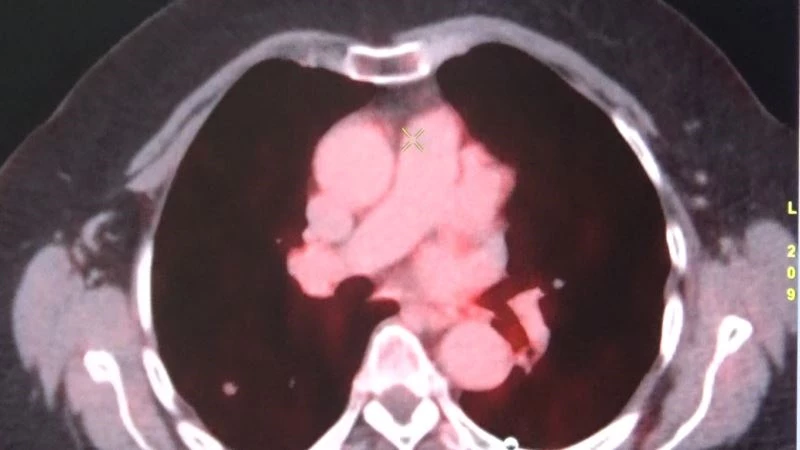

Diyarbakır Gazi Yaşargil Eğitim ve Araştırma Hastanesinde 2010 yılından bu yana hizmet veren Nükleer Tıp Bölümünde birçok hasta radyoaktif tedavisiyle şifa buluyor. Son nükleer tıp teknolojileriyle her türlü sintigrafik görüntülemenin yapıldığı bölümde, kalpten akciğere, karaciğerden kemik ve böbreğe kadar geniş bir alanda teşhis için SPECT/CT, SPECT, PET/CT ve FAPI cihazları kullanılıyor. Bölgenin en büyük etkin nükleer tıp merkezlerinden olan Gazi Yaşaragil Eğitim Hastanesinde 3 doçent doktor ve 5 uzman doktor ile Nükleer Tıp Bölümü hizmet veriyor. Nükleer Tıp Bölümünün sadece sintigrafik görüntülemeden ibaret olmadığını belirten Nükleer Tıp Uzmanı Doç. Dr. Halil Kömek, hastalığın yarısı oranında tedavi ile ilgilenen bir bilim dalı olduğunu söyledi. Kömek, “FDG PET/CT ile onkolojik tüm vücut görüntüleme yapan cihazlarımız mevcut. Prostat kanserleri için 68Ga-PSMA, nöroendokrin tümörleri görüntülemesi için 68Ga (Galyum68)-Dotatate ve ülkemizde birkaç merkezde uygulanan TİTCK (Türkiye İlaç ve Tıbbi Cihaz Kurumu) onaylı olduğumuz FAPI (fibroblast aktivasyon protein inhibitörü) ile kolorektal ve gastointestinal kanserlerinin periton yayılımlarında kullandığımız FAPI görüntülemesi yapmaktayız” dedi.

Hastanede yılda 6 bin hastanın tümör taraması amacıyla PET/BT görüntülemesinin yapıldığını söyleyen Kömek, “Hastanemizde ayrıca tiroid kanseri 300 hastaya İyot tedavisi yapılmakta. Yılda 400 hastaya da Lutesyum tedavileri, prostat kanserlerinin nöroendokrin tümörlerinin ya da ağrı palyasyonu amacıyla uygulanmaktadır. Açılımını yaparsak eğer, radyoaktif madde ile işaretlenmiş bir reseptör bağlacını hastanın vücuduna enjekte ediyoruz ve sadece tümörlü alanları tutup tedavi ediyor. Herhangi bir yan etkisi olmadan sadece tümöre spesifik reseptörlere bağlanarak tedavi edildiği için, hedeflenmiş radyoterapi dediğimiz sistemi kullanıyoruz. Bunun yanı sıra yılda yaklaşık 300 hastanın da hipertiroidi tedavisini yapmaktayız” şeklinde konuştu.